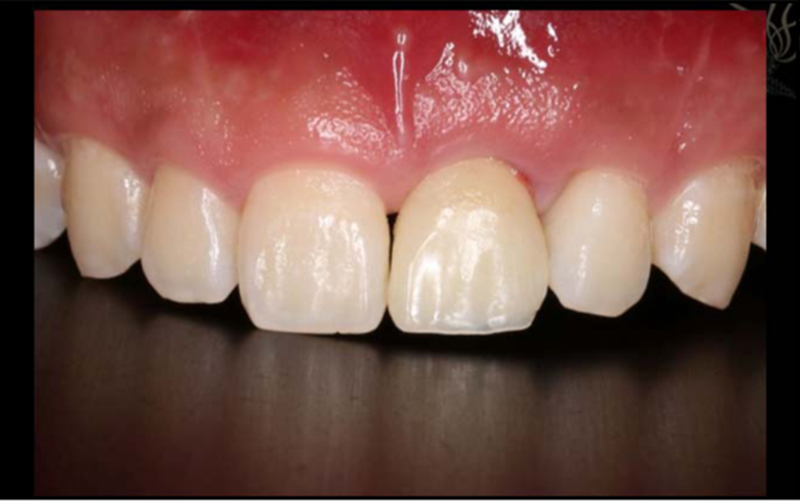

1.使用螺絲固位修復方案 2.軟組織恢復效果佳,達到美學效果

術(shù)后照片